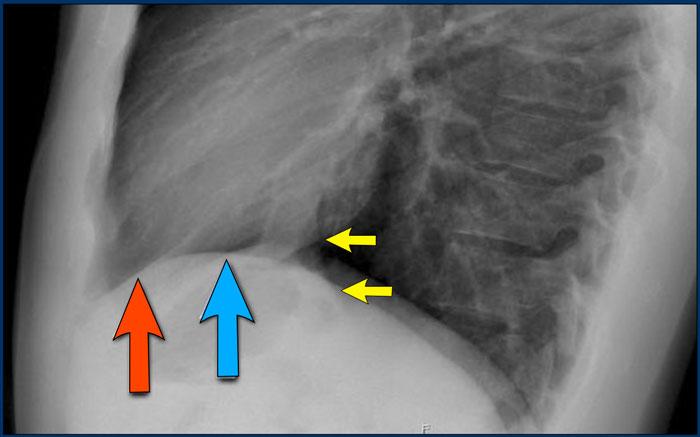

Đánh giá Cơ hoành

- Vòm hoành phải phải được nhìn thấy rõ ràng ở phía trước đến tận thành ngực (mũi tên đỏ), thể hiện ranh giới giữa phổi có khí và mô mềm ổ bụng.

- Vòm hoành trái thường chỉ nhìn thấy đến điểm tiếp giáp với bóng tim (mũi tên xanh lam), phía ngoài điểm đó ranh giới bị mất do tỷ trọng tương đương giữa tim và các tạng bụng phía trên.